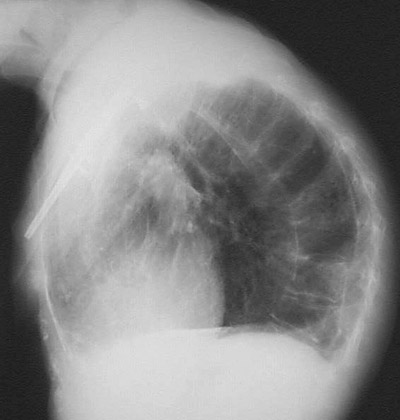

| This lateral chest radiograph demonstrates marked kyphosis of the vertebral column so that the head and neck are bent forward and the total chest volume is markedly reduced. This patient had severe osteoporosis, and a fall resulted in a fracture of the humerus that required open reduction and internal fixation, evidenced by the bright metal rod seen here. |